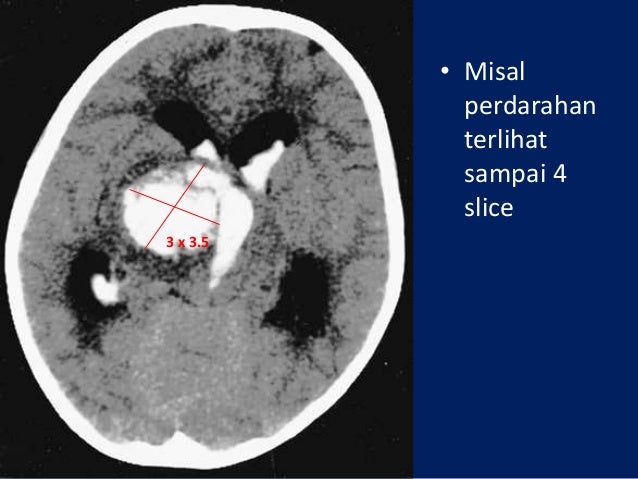

Item Type:Thesis(Skripsi)Additional Information:KKA KK FK.PD.186/17 Dar pUncontrolled Keywords:Subarachnoid Hemorrhage, Age, Gender, Risk Factor, Symptom,Severity, Surgical therapy, OutcomeSubjects:Divisions:Creators:CreatorsNIM/NIDNAhmad Faisal Darmawan, NIM84NIM84Contributors:ContributionNameNIDN/NIDK/NUPContributorAchmad Firdaus Sani, dr., SpS,FINSUNSPECIFIEDContributorWidati Fatmaningrum, Dr., dr,M.Kes,Sp.GKUNSPECIFIEDDepositing User:Mr Binkol1 1Date Deposited: 16:48Last Modified: 16:48URI:Sosial Share.Download Mac OS X Yosemite 10.10.3 latest free latest standalone offline bootable DMG image. SoetomoSurabaya in July 2013 – June 2016 is still high patients who suffer the most based onthe age group are 46 – 65 years old, while based on Sex is Woman. The common causesfor the death of a patient due to Cerebral herniation experienced by 75 patients (80%).The mortality of Subarachnoid Hemorrhage patients in RSUD Dr. Johns Hopkins University J Ricardo Carhuapoma Soetomo still often the case with the number of 94 patients (49%). Because the mortality rate is still quitehigh, outcome death in patients with Subarachnoid Hemorrhage in the Hospital Dr. Coilling method is most commonly usedby patients with a number of 20 patients (91%). Surgical therapy is recordedonly 22 patients (11%) who use this therapy. The number of patientswho had grade 4 WFNS with the number of 82 patients. Loss of consciousness is the most common symptom seen in patientsupon hospital admission with a number of 109 patients (57%). Of the various other risk factors from past medical history, hypertensionis a risk factor that is most commonly experienced by patients with the number of 112patients (73%). The age group 46-65 is the age range most often found with a number of 118patients (62%). The number of female patientsis still dominated with a total of 112 patients (59%), while for males in 79 patients(41%). Soetomo Surabaya in July 2013 – June 2016. Soetomo Surabaya withinJuly 2013 – June 2016.In this research there are 191 patients of Subarachnoid Hemorrhage patients inRSUD Dr. The data collection of this research is totalsampling of Subarachnoid hemorrhage patients in RSUD Dr. This researchis an observational – descriptive research. Soetomo Surabaya within July 2013 – June 2016. Official URL:AbstractSubarachnoid Hemorrhage is a significant cause of mortality and morbiditythroughout the World and patients who survive usually experience neurological deficit.In addition it happens frequently in women.This research is aimed to find the clinical profile of Subarachnoid Hemorrhagepatients in RSUD Dr.